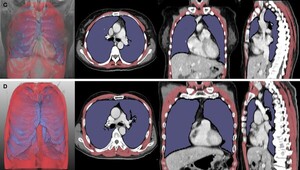

서울대병원 연구팀이 딥러닝 기술을 활용해 루게릭병(ALS) 환자의 흉부 CT 영상에서 폐와 호흡근의 용적 지수를 분석하고, 이를 통해 환자의 병기 및 생존 기간을 예측할 수 있는 새로운 지표를 개발했다. 이번 연구는 기존 폐활량 검사의 한계를 보완할 수 있는 대안으로 주목받고 있다.